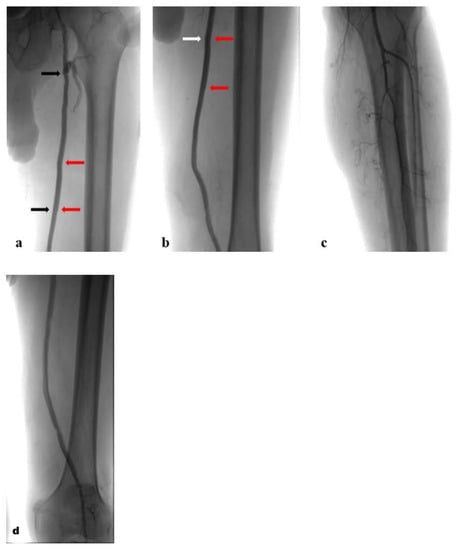

The completion arteriogram showed the resolution of the occlusion with the direct and increased distal flow without any complications (Figure 4a–d). Successful haemostasis with FemoSeal (Terumo Europe) was obtained. The stent graft has adapted perfectly to the morphology of the lesions to be treated. The popliteal artery was reperfused to the third proximal through the collateral vessel; the vessel did not show significant atheromatous plaques. After treatment, the patient underwent therapy with clopidogrel (75 mg) + ASA (100 mg) for 2 months; next with only ASA (100 mg). Color Doppler Ultrasound after 1-3-6-9-12 months from the procedure showed patent self-expanding stent graft inside the excluded PA (Figure 5).

Figure 4. Postoperative angiograms with self-expanding stent grafts inside the prosthetic FB bypass: (a). proximal stent graft (black arrows) and overlap (red arrows); (b). overlap (red arrows) and distal stent graft (white arrows); (c,d). run-off.